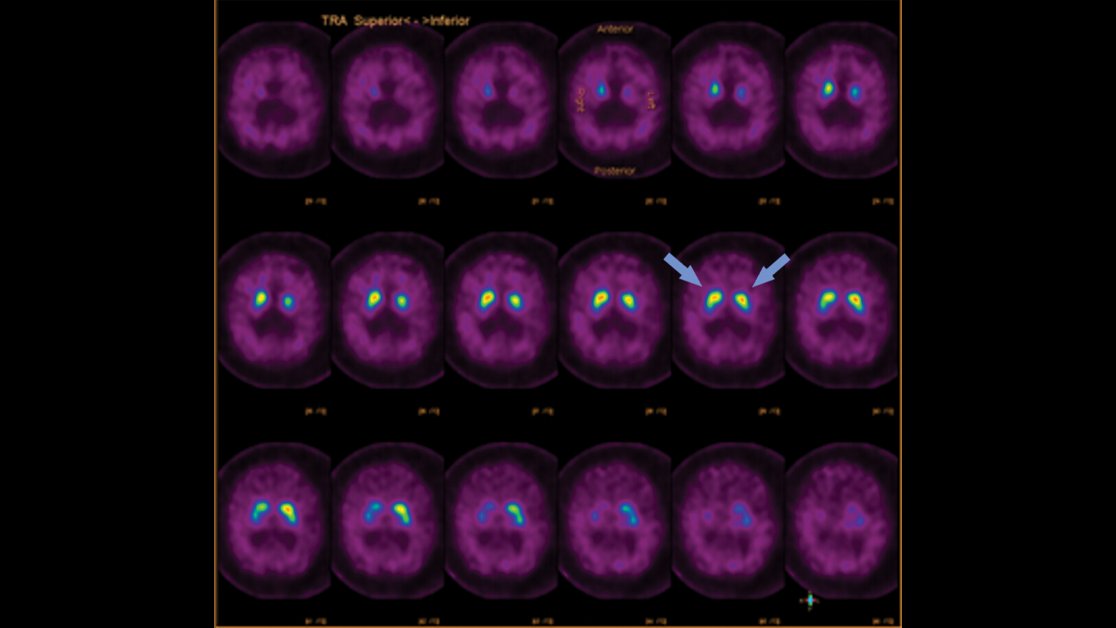

Border zone infarcts often tell a story. Unilateral cerebrum? Think proximal stenosis. Bilateral cerebrum & cerebellum? Think systemic event. In this case, nasopharyngeal ca → ICA occlusion → symptomatic border zone infarcts. See http://bit.ly/2Sdu5xa to learn more!pic.twitter.com/7fYYg8aReq